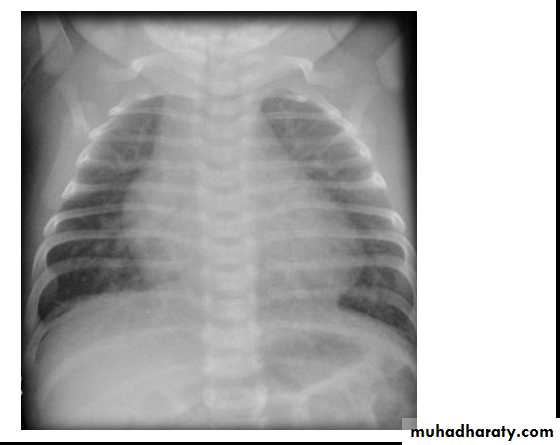

CXR: shows cardiomegaly, Rt atrial enlargement, prominent pulmonary artery and increased pulmonary

CXR: may be normal in small VSD, but in large VSD there is may be cardiomegaly and increased pulmonary vascularity.